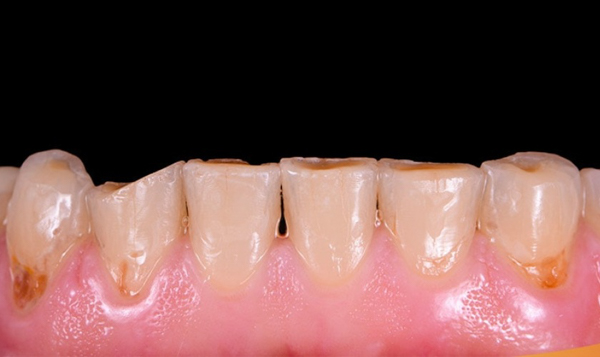

Men răng là lớp bảo vệ cứng nhất của răng, giúp bảo vệ phần ngà răng bên trong. Tuy nhiên, theo thời gian, men răng có thể bị mòn đi do nhiều yếu tố như ăn uống đồ ăn, thức uống có tính axit cao, chải răng quá mạnh, hoặc lão hóa. Khi men răng bị mòn, răng cửa sẽ trở nên yếu hơn và dễ bị mẻ hơn khi gặp các tác động từ bên ngoài.

Mòn men răng